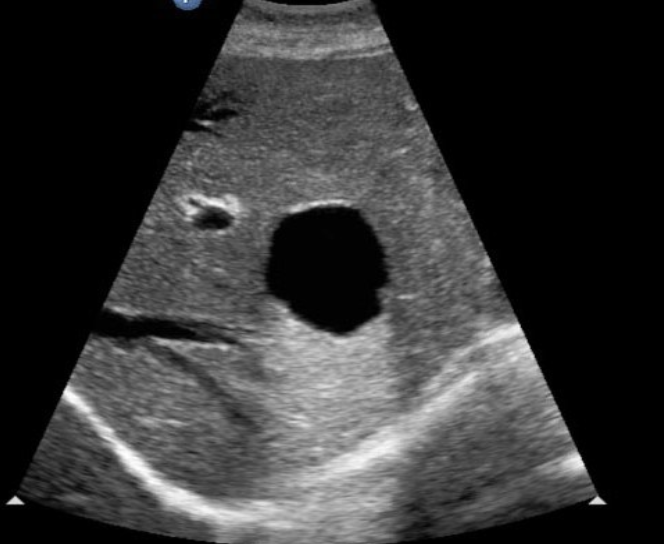

2D US: anechoic, well-defined smooth, thin wall, round or ovoid, posterior enhancement

color doppler: avascular

Simple Renal Cyst → common lesion of kidney, fluid-filled sac (benign, Bozniak 1)

clinical hx: incidence increases with age (50+), uncommon in children

s/sx: asymptomatic